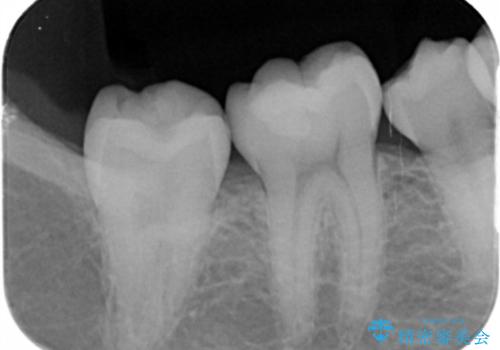

古い樹脂の詰め物を取り除いたところ、歯の神経と非常に近い状態でした。

万一神経と交通した場合に備え、唾液が入らないようにゴムのシートで防湿(ラバーダム防湿)を行い虫歯除去を行いました。

幸い神経とは交通せず、処置後の神経症状もありませんでした。